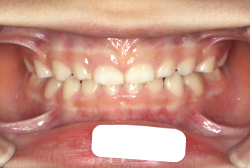

凸凹な歯並びのことを叢生といいます。矯正歯科に来院する患者様の主訴の中で、最も多いのが「配列の凸凹を真っ直ぐにしたい」というものです。歯の大きさと顎の大きさの調和がとれていないことが原因です。

凸凹を主体としたケースの場合、当院の平均治療期間は18ヶ月ですので、このケースは少し長めに経過しました。理由の一つは凸凹の程度がかなり重症だったと言うことですが、もう一つは、右下第2大臼歯が45度くらい前傾していたため、それを整直化させるために時間を要したと考えています。いずれにしても最終結果は大変よい状態と思います。

治療前は並びが乱れて見た目が悪いというのはもちろん問題ですが、歯科医学的に一番困るのは噛み合わせが悪いという点です。上下の犬歯(3番目の歯)は、上下的に離れた位置にあるため接触することができません。つまり歯としては存在していても、歯としては機能していないということです。